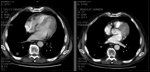

FIGURE 1

CT Scan Example of Responder

No grade 3 or 4 toxicities were encountered for the initial 10 cases. Response rate for 10 evaluable patients was 50%, with 5 partial responses. Time to progression for the 10 cases is shown in Table 1. The median time to progression was 8 months, which is a minor improvement over the median survival of 7.5 months reported by Atkins et al for a biochemotherapy regimen that substituted oral temozolomide (Temodar) for dacarbazine.[25] A CT scan showing evidence of a partial response in one study subject is shown in Figure 1.